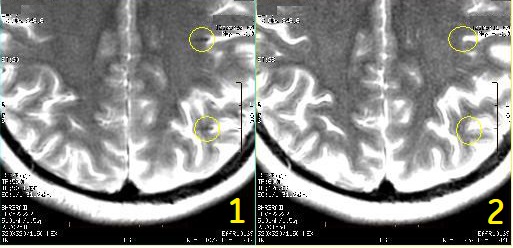

Top of scalp artifacts

Top of scalp artifacts are caused by not having enough data to perform motion correction.

Prescribe fewer slices to cover only anatomy of interest.

| 1 | Top of scalp |

| 2 | Extreme top of scalp displaying white pixels |

| 3 | Extreme top of scalp displaying noise and white pixels |